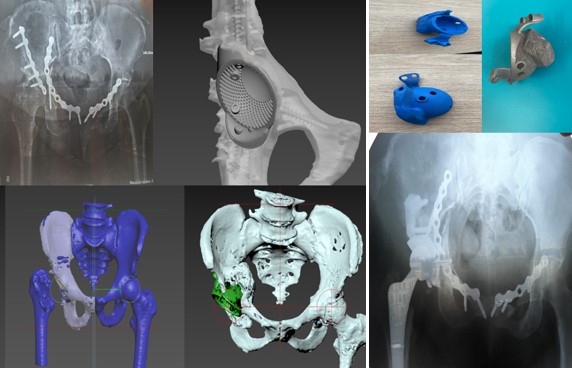

Приклад заміщення дефектів кісток тазу при ураженні пухлиною. Складне індивідуальне ендопротезування кульшового суглоба

ЕТАПИ ПРОЕКТУВАННЯ ІНДИВІДУАЛЬНИХ РЕВІЗІЙНИХ СИСТЕМ

Розрахунок розміру компонента, імплантація ревізійної ацетабулярної системи, Розмір трансплантованої кістки з використанням опорних площ, доповнюючи масивною кістковою пластикою дефектів з метою відновлення рекомендованої позиції компонента

Пацієнт С-к Роман Михайлович, 1975 рік. Травма в результаті ДТП (7.10.2023 р.) – перелом заднього краю лівої кульшової западини зі зміщенням. Післятравматичний лівобічний коксартроз 4 ст., стан після МОС заднього краю лівої кульшової западини пластиною та гвинтами. Згинально-привідна контрактура зліва. Наслідки ушкодження лівого сідничного нерва в лівій сідничній ділянці. Стан після встановлення ЕСС “НейСі-3М” на малогомілковий (CPN) та великогомілковий (TN) нерви в н/3 лівого стегна.

Операція: Вилучення металофіксаотора. Повна артропластика лівого кульшового суглоба з індивідуальним ацетабулярним компонентом

Пацієнт С-к Роман Михайлович, 1975 рік. Травма в результаті ДТП (7.10.2023 р.) – перелом заднього краю лівої кульшової западини зі зміщенням.

Післятравматичний лівобічний коксартроз 4 ст., стан після МОС заднього краю лівої кульшової западини пластиною та гвинтами. Згинально-привідна контрактура зліва. Наслідки ушкодження лівого сідничного нерва в лівій сідничній ділянці. Стан після встановлення ЕСС “НейСі-3М” на малогомілковий (CPN) та великогомілковий (TN) нерви в н/3 лівого стегна.

Спроектована та імплантована індивідуальна, пориста, титанова, 3D-друкована кульшова западина, фіксована гвинтами.